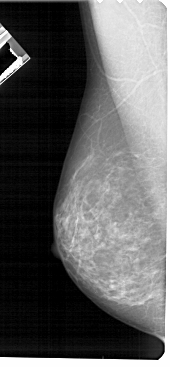

A_1715_1.RIGHT_CC

RIGHT_CC LINES 4591 PIXELS_PER_LINE 2251 BITS_PER_PIXEL 12 RESOLUTION 43.5 OVERLAY